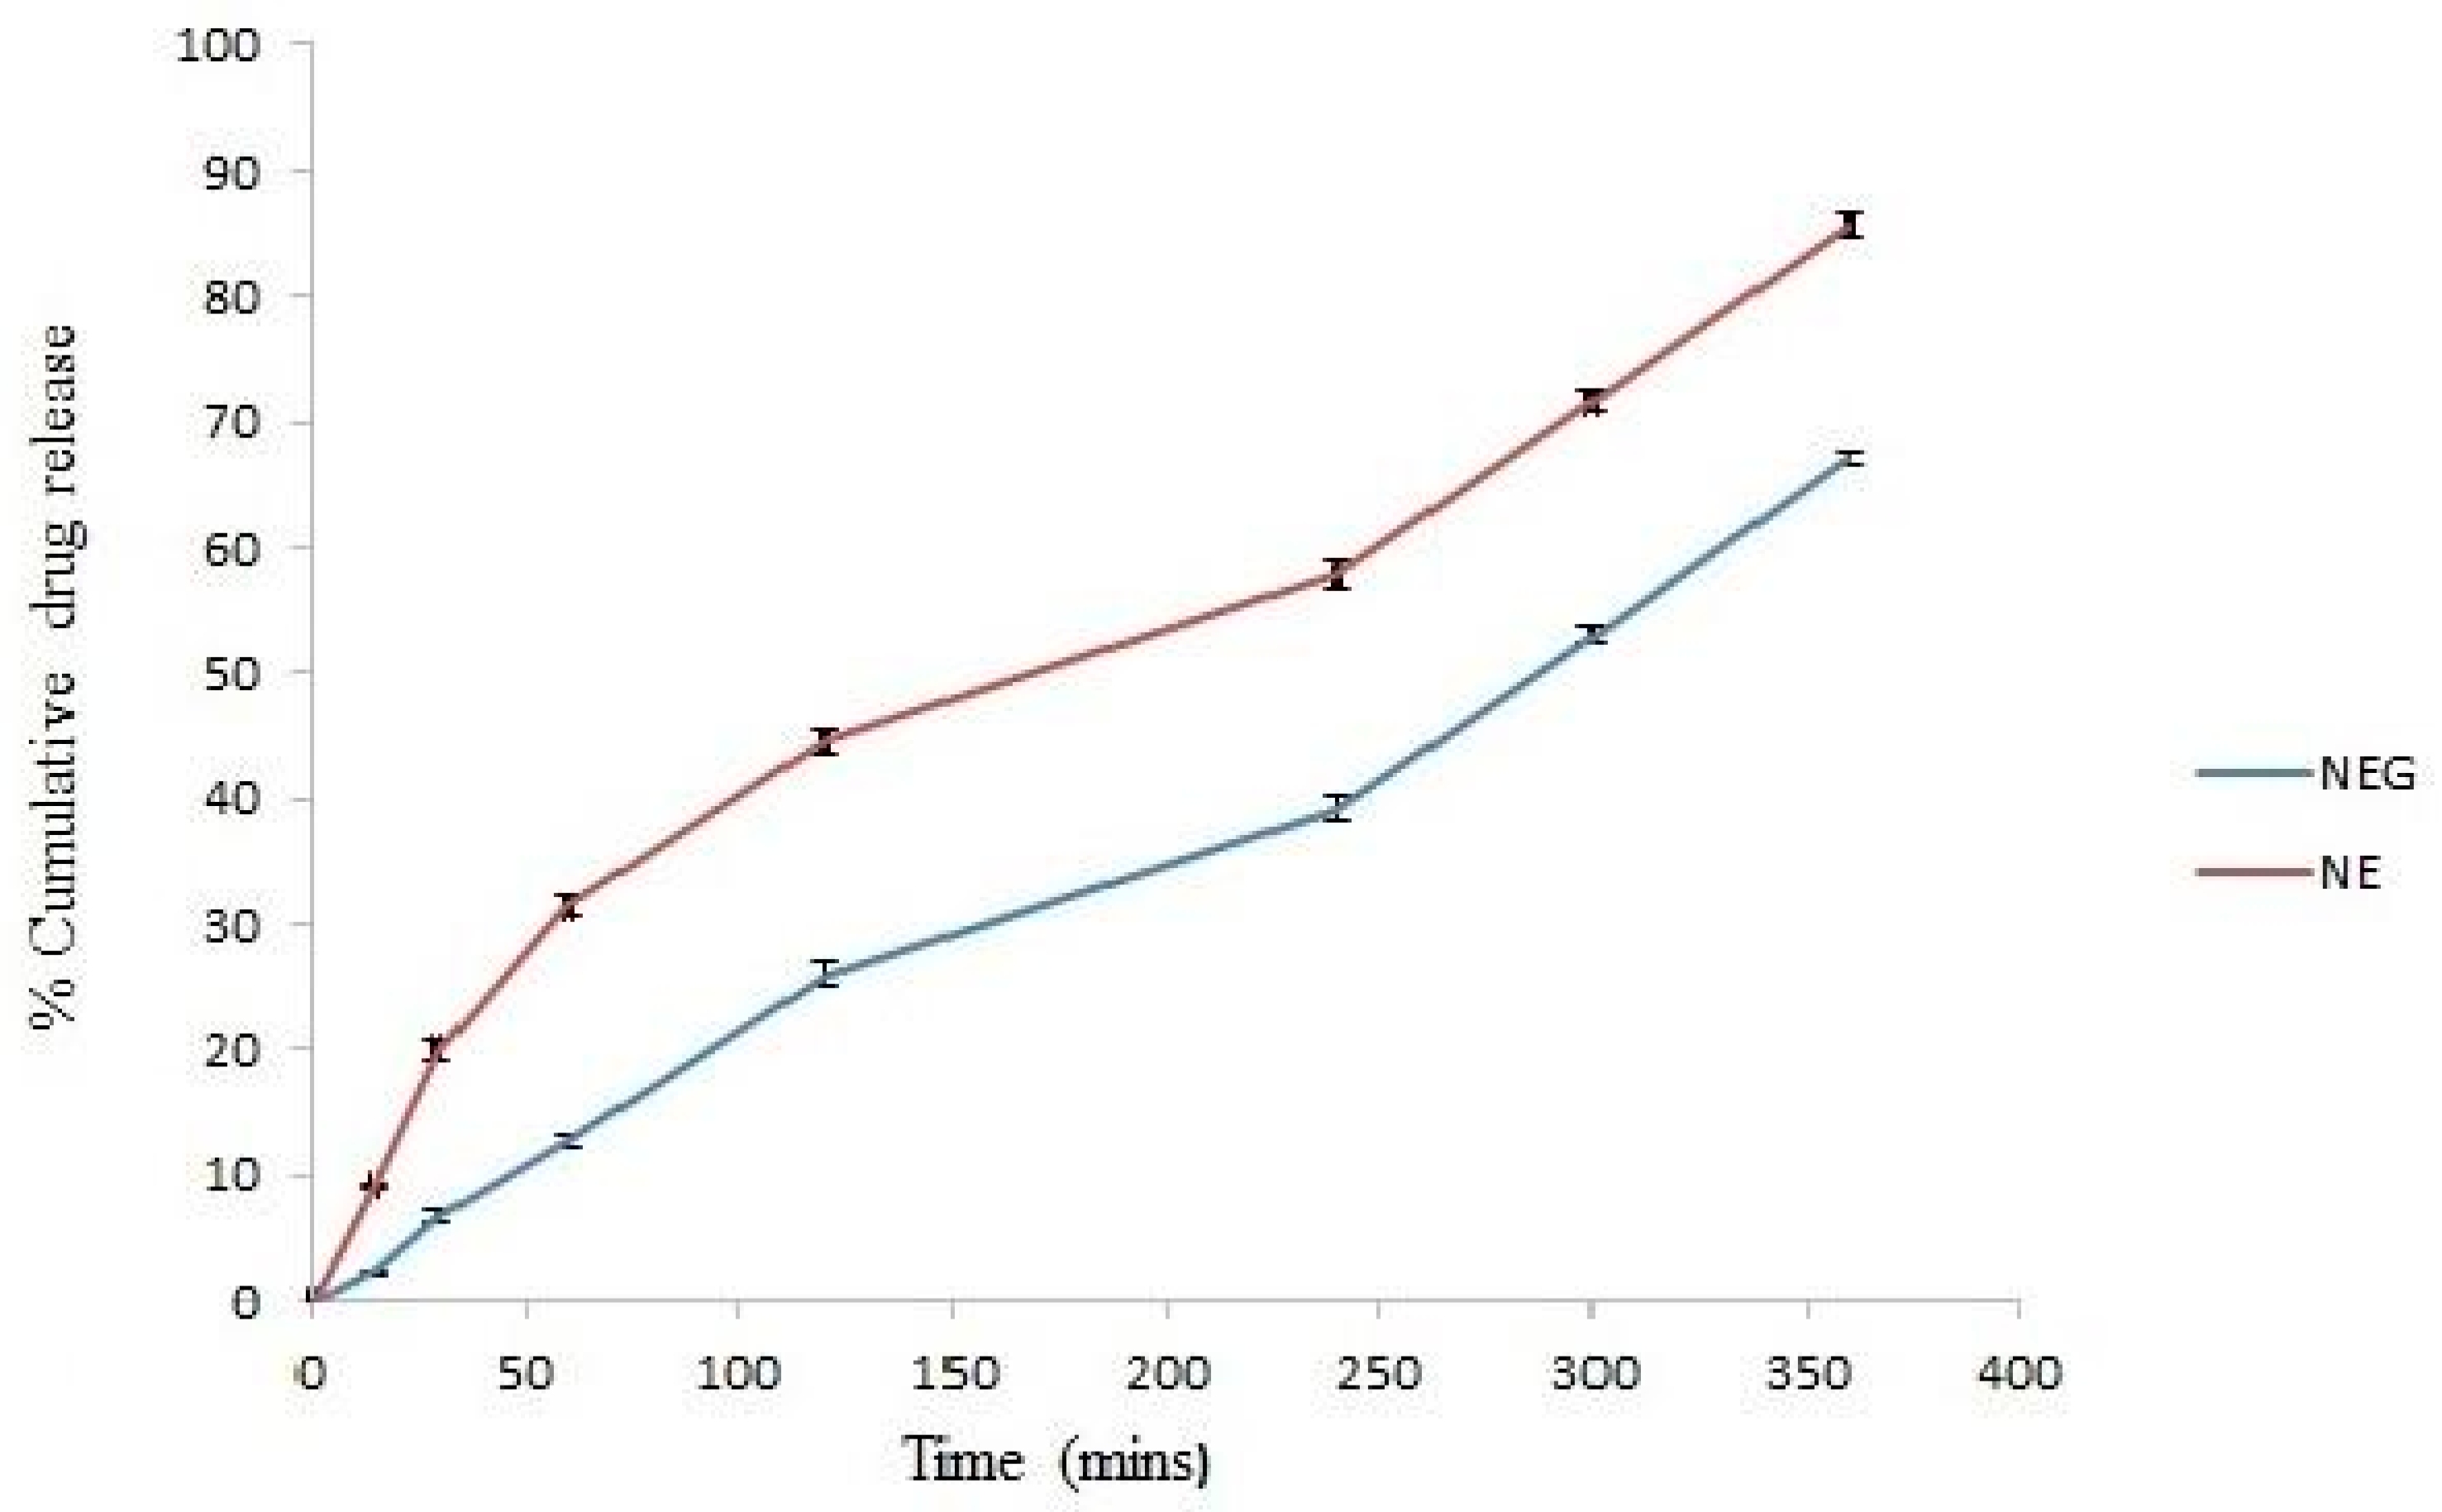

3.8. In Vitro Drug Release